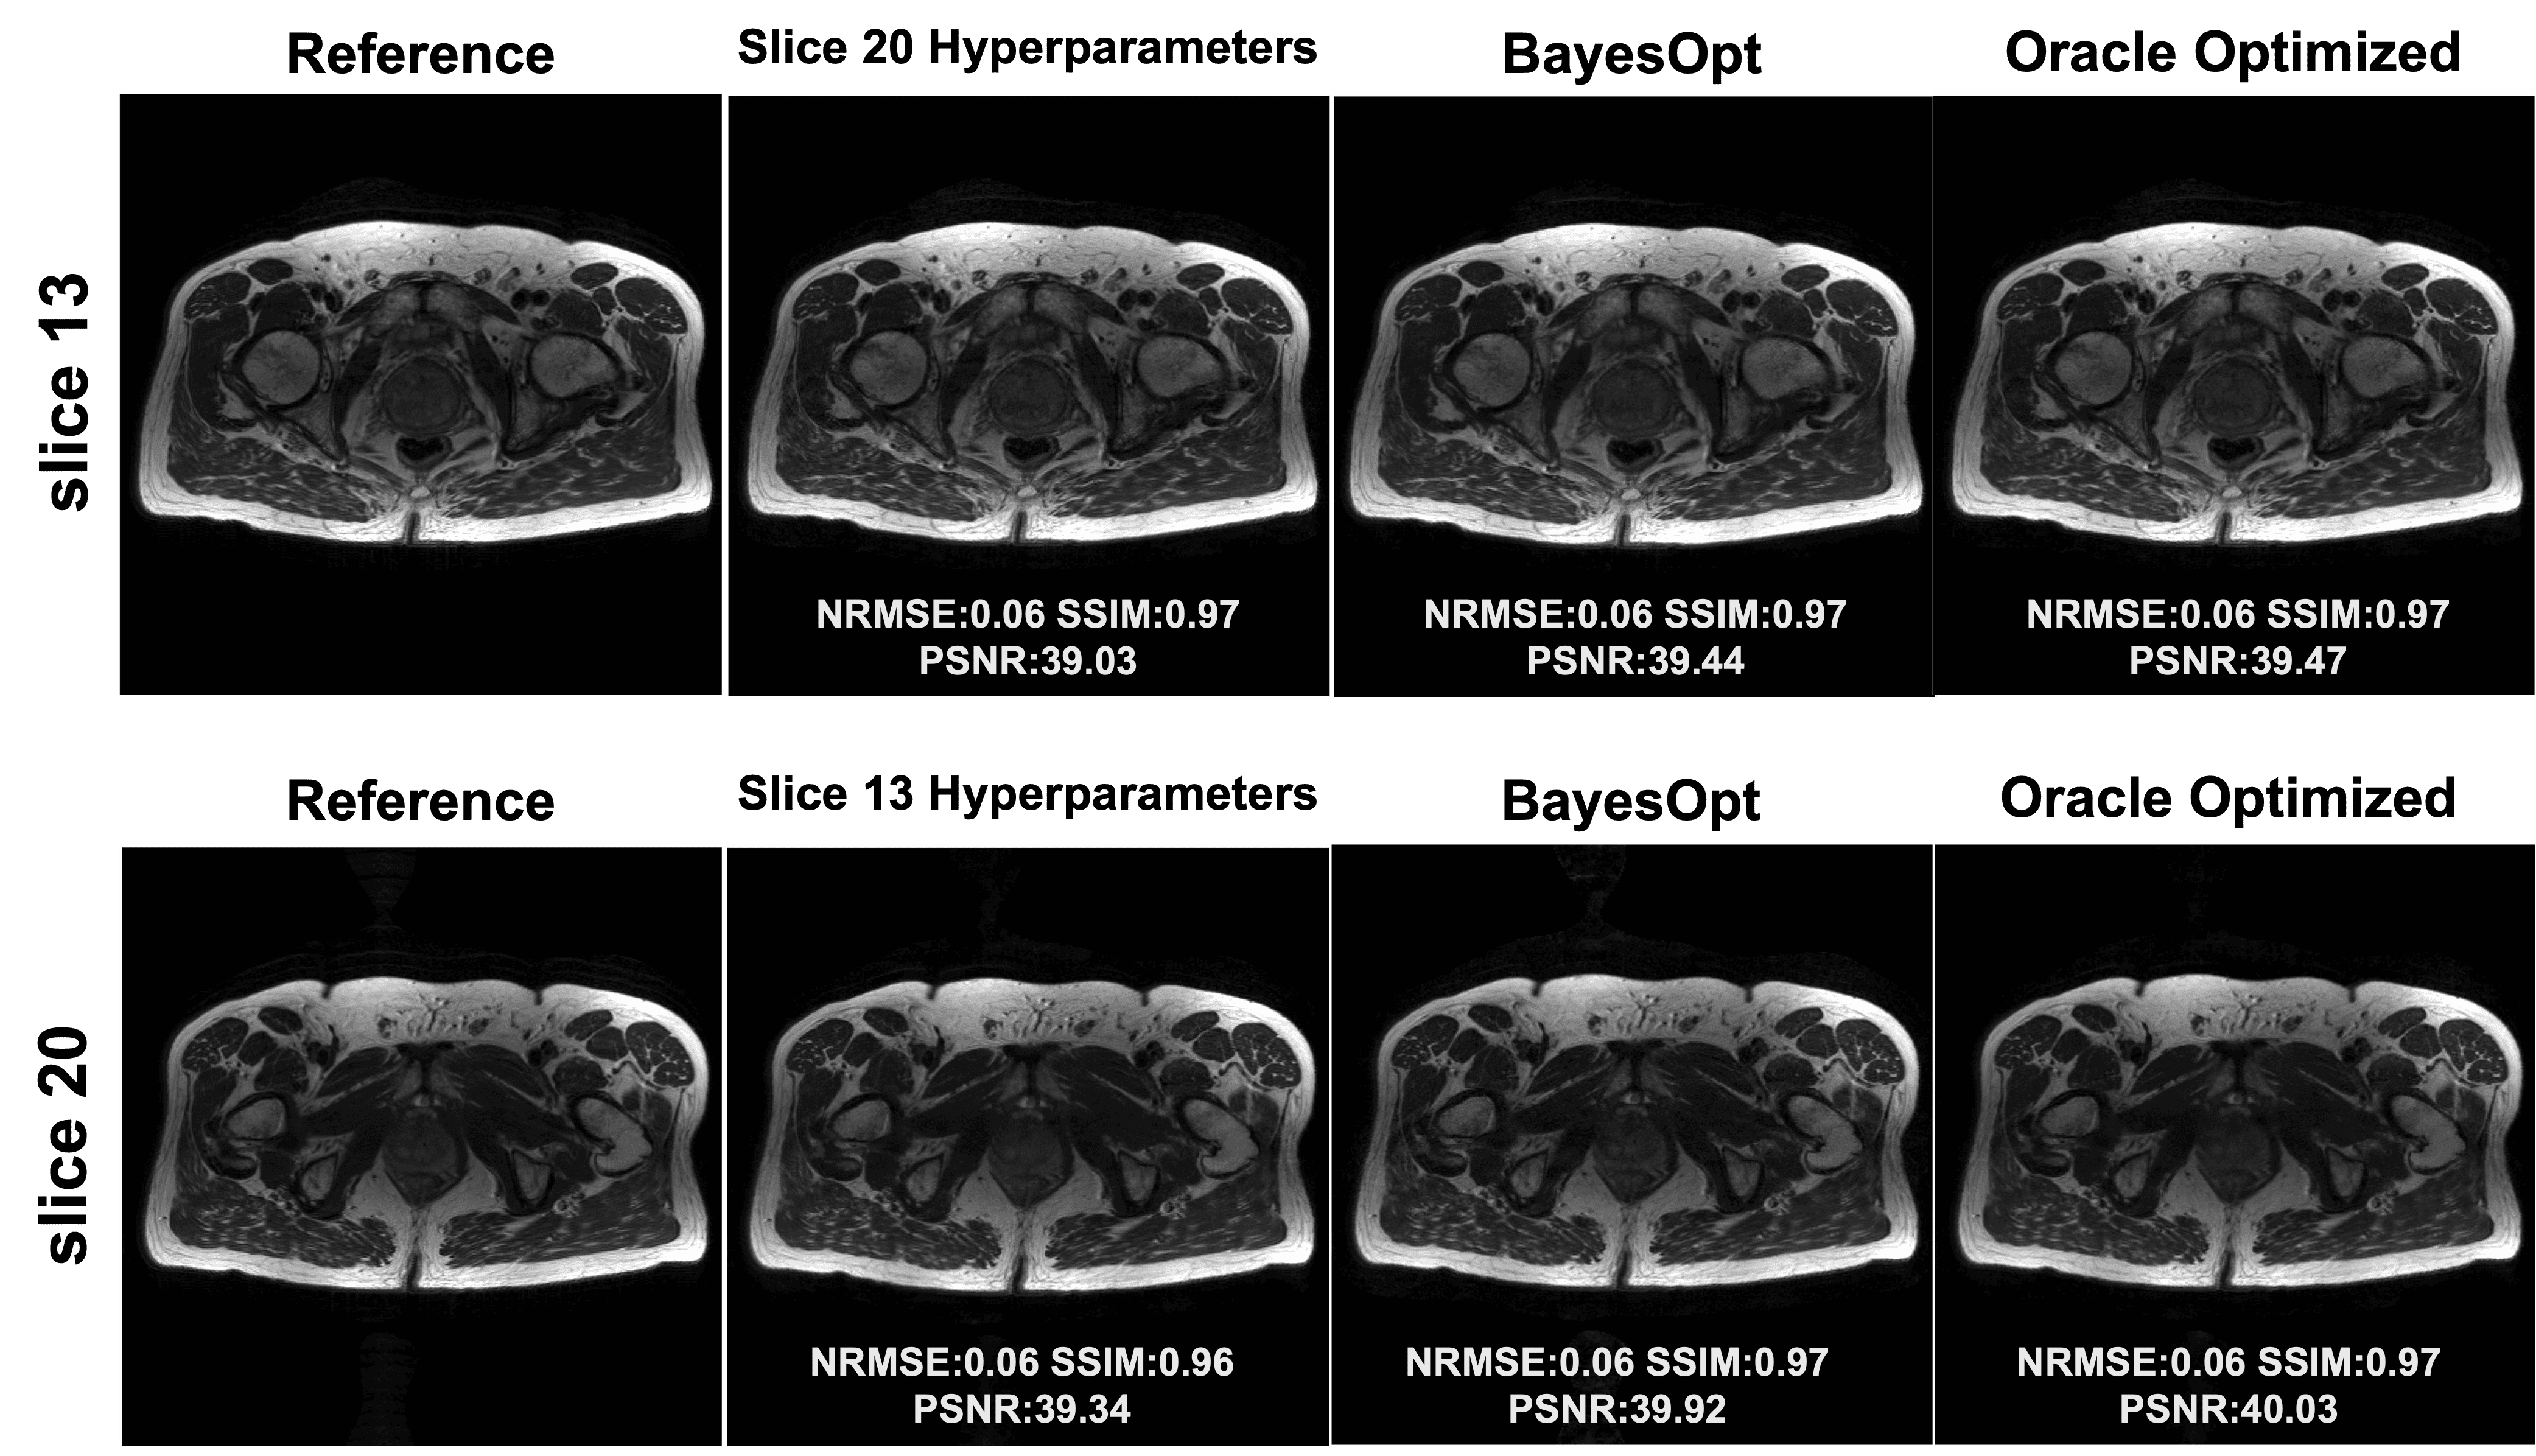

Figure 5: Demonstration of hyperparameter optimization using Bayesian Optimization. (a) and (b) show comparisons of bSSFP acquisitions at acceleration factors R=6R=6 and R=8R=8 for volunteer 1. (c) shows comparison of bSSFP acquisition for volunteer 2 at R=6R=6, illustrating that hyperparameters are transferable to a different subject for the same imaging sequence. (d) shows a comparison of a T2w TSE acquisition from volunteer 1 in (a) at R=6R=6, illustrating that different sequences require tailored hyperparameter optimization. Acquisition parameters are provided in Table 1.

Refer to caption

Figure 6: Demonstration of hyperparameter transferability. Reconstructions of two slices from a multislice prostate acquisition are shown (6×6\times Cartesian undersampled). Each slice is reconstructed with both its own optimized hyperparameters and those from the other slice, indicating that the optimized hyperparameters are transferable across similar anatomy under the same acquisition.

Fig. 5 illustrates the hyperparameter optimization results. Fig. 5(a) and (b) show that Bayesian optimization yields nearly optimal results compared to the oracle optimization across NRMSE, SSIM, and PSNR for both R=6R=6 and R=8R=8 on volunteer 1. By contrast, empirical tuning leads to residual artifacts near the brain center. The empirically tuned hyperparameters were chosen based on previously successful reconstructions for other sequences and resolutions. Table 2 lists the hyperparameter values in each case. Except for the loss-weighting controller δ\delta, all other hyperparameters differ between R=6R=6 and R=8R=8, indicating that each sampling pattern benefits from a tailored optimization.

Fig. 5(c) displays the reconstruction of the same bSSFP sequence with identical acquisition parameters and similar slice position for volunteer 2. Bayesian optimization achieves performance comparable to oracle optimization across all metrics. The hyperparameters optimized for volunteer 1 adapt well to volunteer 2, with similar NRMSE and SSIM, and only slightly worse PSNR, showing that hyperparameters optimized for bilevel INR can be transferred between similar acquisitions.

Fig. 5(d) uses a T2-weighted TSE scan from volunteer 1 at the same slice position to demonstrate the sequence dependence of INR-based reconstruction. The performance using hyperparameters optimized for the bSSFP scan of volunteer 1 is 5.415.41 dB worse in PSNR and 0.050.05 higher in NRMSE compared to tailored Bayesian Optimization. The resulting images appear more blurry because bSSFP sequences generally have lower SNR than TSE, and optimizing for bSSFP tends toward stronger denoising (e.g., λEnc=2.6e4\lambda_{\mathrm{Enc}}=2.6e-4 in (a)). In contrast, T2-weighted TSE scans keep anatomical structures more clearly and thus need less regularization (e.g., λEnc=1.2e5\lambda_{\mathrm{Enc}}=1.2e-5 in (d)) .

Fig. 6 further demonstrates the transferability of hyperparameters across anatomically similar regions. Reconstructions for two 6×6\times undersampled pelvic slices are compared using both tailored hyperparameters (optimized specifically for each slice) and hyperparameters transferred from the other slice. The transferred hyperparameters yield good reconstructions, with only small decreases in PSNR (0.41 dB and 0.58 dB, respectively) compared to the tailored results.